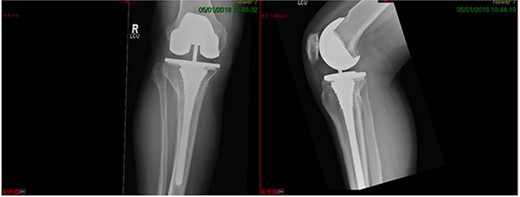

A 68-year-old gentleman who was diagnosed with a Schatzker type VI fracture having fallen 3 m from a ladder (Figs 1 and 2). The injury was closed and neurovascularly intact. The patient was monitored for signs of compartment syndrome. He rapidly developed significant fracture blisters that persisted for over 2 weeks despite regular dressing care. He was deemed too high risk for acute operative intervention because of a high risk of wound complications. Following a multidisciplinary team discussion, he was managed in a cast then a knee brace, mobilising non weight bearing for 12 weeks, at which point the fracture was seen to be healing in a valgus malalignment. The patient was allowed to partially weight bear and received physiotherapy. He was reviewed regularly until fracture had united (Fig. 3). At 8 months post-injury, the patient underwent total knee arthroplasty utilizing a Depuy Synthes (Warsaw, In) PFC Sigma TC3 tibial metaphyseal sleeve and stem, and femoral component without sleeve or stem (Fig. 4). The patient was reviewed post-operatively in clinic at 6 months, the wound had fully healed and the range of motion was 0°–120°. The patient’s pain was significantly reduced, and they were independently mobile. They were kept under annual review and seen at 5 years post-operatively with an Oxford Knee score of 35; the patient used no walking aids and was pain free at rest or during normal walking, with the radiograph demonstrating good osseointegration. The latest follow-up at 8 years revealed no radiographical change in implant (Fig. 5).